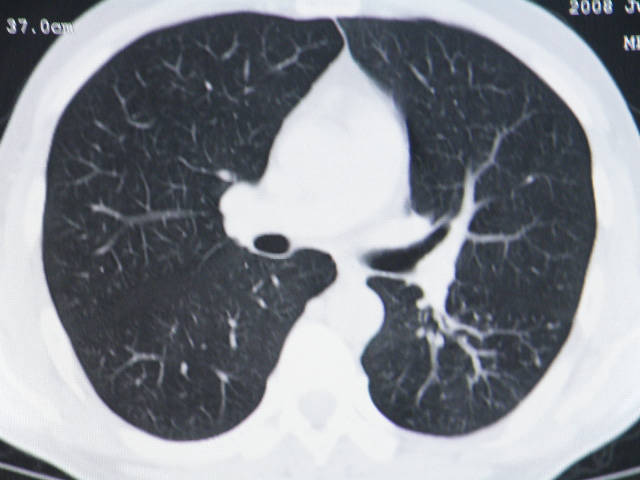

肺内结节在纵隔窗内测ct值为43hu

左肺下叶背段软组织结节,偏心空洞,周围见长纤维所条及卫星灶,首先考虑结核球,周围型肺癌待排。

左肺下叶偏心软组织肿块,边缘毛刺征,胸膜凹陷征

有肝硬化背景,肝胃间隙见不规则形,且密度不均匀的占位性病变,与肝左叶分界不清,首先考虑外生性肝癌可能性大,不排外肝胃间隙恶性占位肝脏受侵可能性。左肺下叶结节影,其内见空泡征,边缘见毛刺,从一元化的角度首先考虑转移。

1 肝脏各叶比例失调,形态失常,外缘呈波浪状。右叶萎缩,左叶 尾叶增大。2 腹腔内软组织密度肿块,低于肝实质密度,内见低密度区,并与肝脏界限欠清。腹膜后见肿大淋巴结,并与腹腔肿块关系密切。3 左肺下叶肿块,见边缘毛刺征及胸膜凹陷征,并与近肺门侧见异常血管相连。

左肺下叶偏心软组织肿块,边缘毛刺征,胸膜凹陷征,血管集束症

1肝胃韧带区域一肿块,肿块上缘与肝左叶相连。肝硬化。考虑肝外生型肝癌可能性大,不除外间质瘤。2左肺下叶背段一结节,有偏心性空洞,长毛刺,其周有多发小结节。考虑结核可能性大。

那肺内病灶如何处理?

肝脏考虑外生型肝癌、肺内考虑结核,应该增强扫描